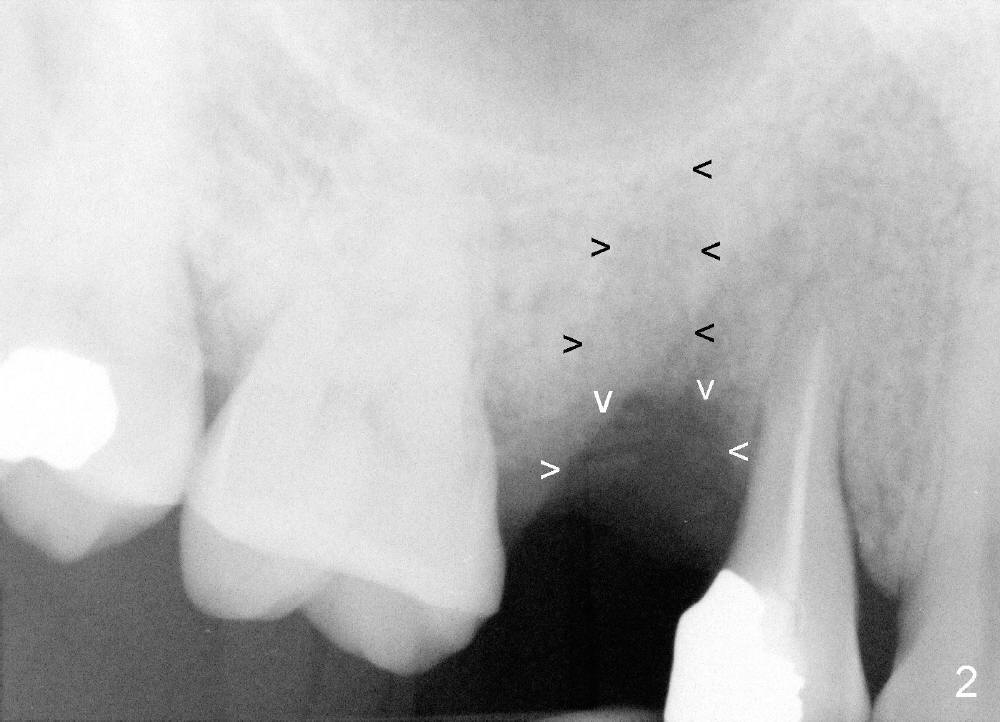

A few months after cementation of implant (Fig.1 I) crown (C) at #30, a 44-year-old man fractured the tooth #4 with MOD amalgam (S) and root canal thereapy (<) while he was visiting his home country. Fig.2 shows the socket (black arrowheads) and bony defect (white arrowheads).